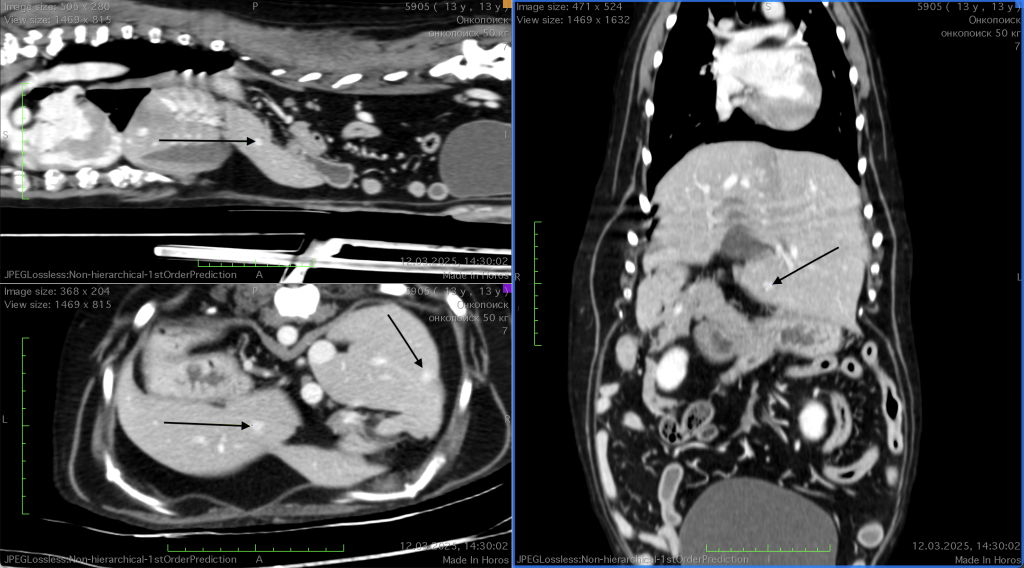

Актуальность. Гемангиосаркома (ГСА) селезенки у собак представляет собой злокачественное высокоагрессивное опухолевое заболевание с ранним метастазированием. Гемангиосаркома поражает преимущественно породы собак средних, крупных и гигантских размеров, а также их метисов. Стандартом лечения ГСА селезенки является спленэктомия с последующей адъювантной химиотерапией, однако прогноз остается осторожным, несмотря на проводимое лечение. Липосомальный доксорубицин (ЛД), обладающий способностью к селективному накоплению в опухолевой ткани и сниженной кардиотоксичностью, представляет интерес в лечении диссеминированных форм ГСА.Цель. Предоставить описание клинического случая применения ЛД у собаки с метастатической ГСА селезенки, оценить его эффективность и безопасность ЛД в сравнении со стандартным доксорубицином, включенным в комплексный противоопухолевый протокол VAC.